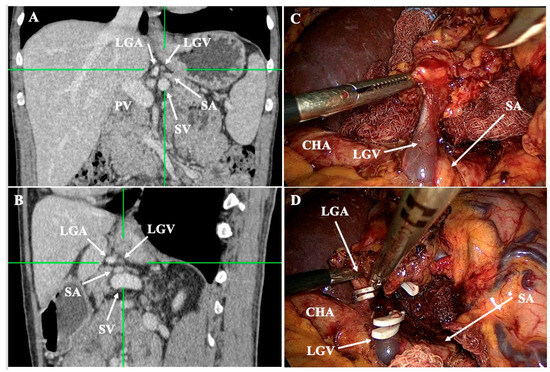

- Lesser curvature and suprapancreatic corridor (stations 7, 8a, 9, 11p): the LGV most often courses posterior to the CHA or anterior to the LGA; recognizing this pattern helps avoid avulsion during high ligation of the LGA and station-7 dissection [30]. Classify the LGV preoperatively relative to the CHA/SA/pancreas. Intraoperative video-based classification in 217 laparoscopic radical gastrectomy cases found type I (LGV running between the CHA posteriorly and the CA-Figure 4) to be most common (56%), whereas type IV (between SA posteriorly and CA-Figure 5) carried the highest bleeding risk (42%) and was an independent predictor of LGV injury on multivariable analysis [32,45] (Figure 4 and Figure 5). 3D MDCT classifications also emphasize that the LGV may terminate variably into the PV, SV, or their confluence—information that guides safe exposure at the pancreatic head and coeliac axis [40]. When a replaced/accessory left hepatic artery arises from the LGA, D2 dissection must preserve arterial inflow while clearing nodal tissue—an approach illustrated in operative atlases focused on variation-aware D2 technique [6].